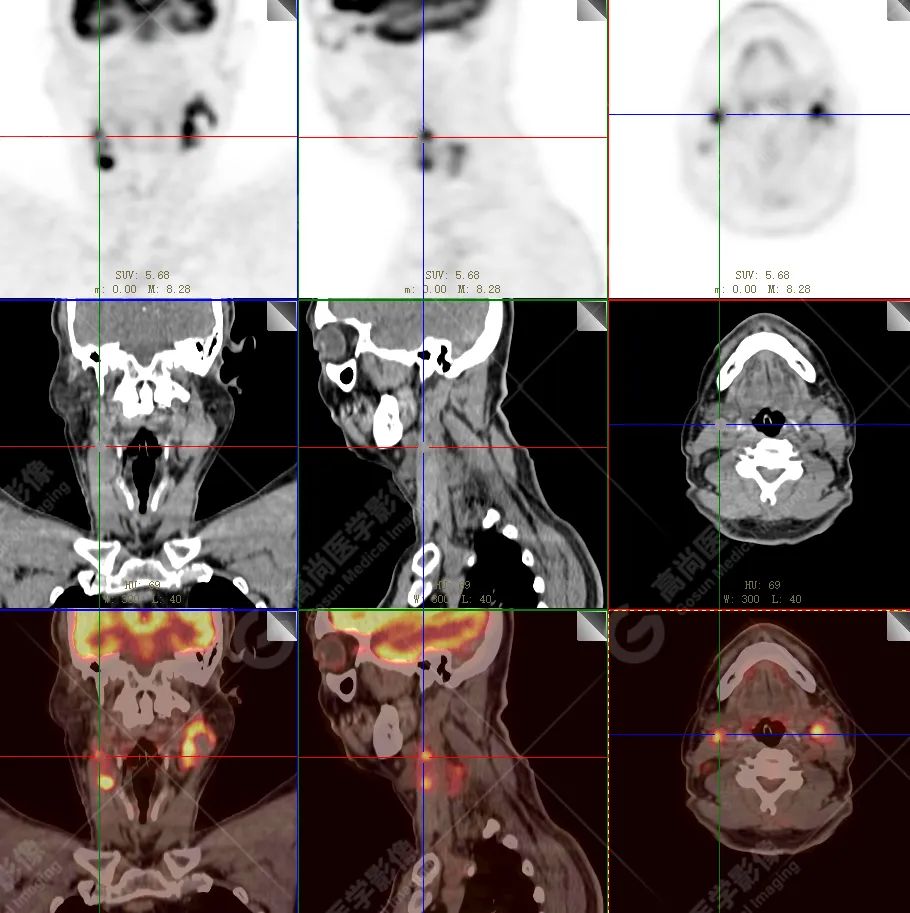

PET/CT 示:

上腭前部见一结节状放射性摄取增高影,大小约 1.6 cm×1.4 cm×1.0 cm,SUV 最大值为 10.5,CT 于上述部位见软组织密度影,边界不清,CT 值约 73 Hu(假牙金属伪影较多致 CT 值偏高)。右侧颈部(Ⅱ、Ⅲ区)及左侧颈部(Ⅰb、Ⅱ、Ⅲ区)见多发结节状及块状放射性摄取增高影,最大约 2.7 cm×2.6 cm×3.1 cm,部分放射性摄取增高,SUV 最大值为 17.7,部分病变内见放射性减低区,CT 于上述部位见增大淋巴结影。

PET/CT 结论:

1. 上腭前部结节状高代谢病灶,多考虑为恶性肿瘤(结合病史,较倾向于黑色素瘤),请结合病理学检查。

2. 右侧颈部(Ⅱ、Ⅲ区)及左侧颈部(Ⅰb、Ⅱ、Ⅲ区)多发淋巴结转移。

病理结果:

恶性黑色素瘤。